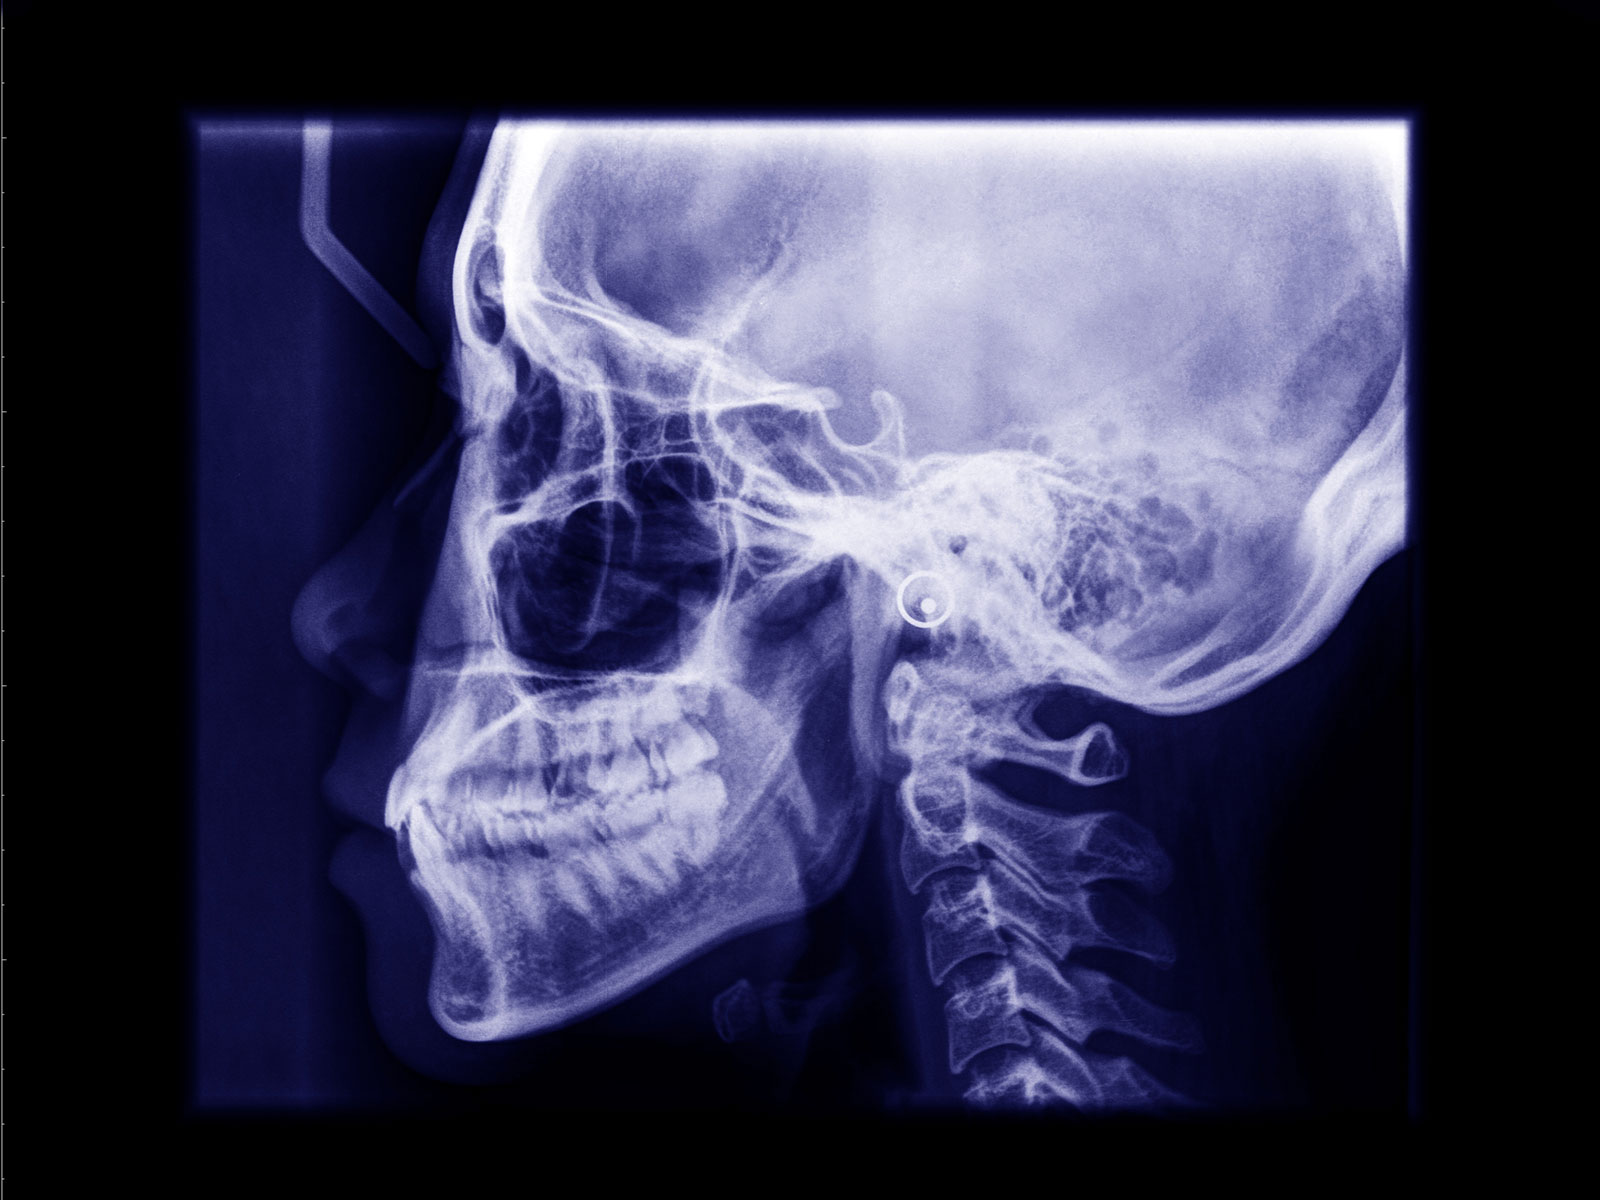

Orthognathic Surgery

Orthognathic surgery involves the surgical manipulation to correct a wide range of minor problems with the jaw and facial structure caused by growth, sleep apnea, TMJ disorders, imperfect positioning of the teeth or other orthodontic problems that cannot be fixed with braces. Surgery can help improve a person’s speaking, chewing and breathing.